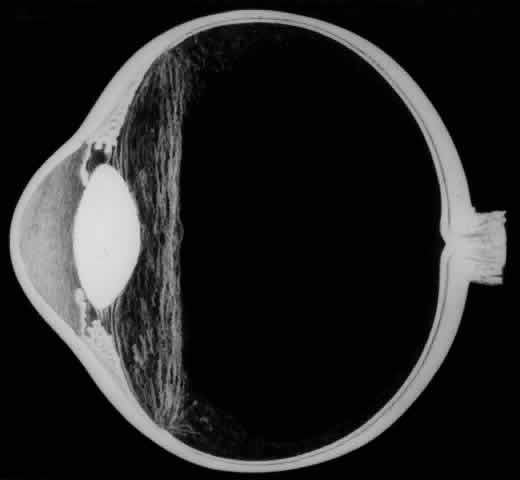

Biomicroscopic Findings Preceding Development of a Giant Tear

The earliest biomicroscopic changes preceding the development of a giant retinal tear were syneresis and liquefaction of the vitreous gel, converting the posterior and central portions of the vitreous body into a large lacuna (Fig. 14). Later, the anterior gel became condensed, and its posterior aspect formed an equatorially oriented membrane extending across the vitreous cavity (Fig. 15). This membrane did not oscillate with ocular movements, suggesting that it was under tension. Marked contraction of this membrane seems responsible for tearing the retina along the posterior border of the vitreous base (Fig. 16). Liquefied vitreous gel facilitated inversion of the posterior retinal flap (Fig. 17).

Fig. 14. The earliest biomicroscopic change in the vitreous prior to the development of a nontraumatic giant retinal break is liquefaction of the vitreous gel, which converts the central portion of the vitreous gel into a large lacuna.

Fig. 15. In later biomicroscopic changes preceding a nontraumatic giant retinal break, the anterior vitreous gel becomes condensed and a membrane forms its posterior aspect.

Fig. 16. Contraction of this equatorially oriented membrane extending across the vitreous cavity produces a giant tear along the posterior border of the vitreous base.